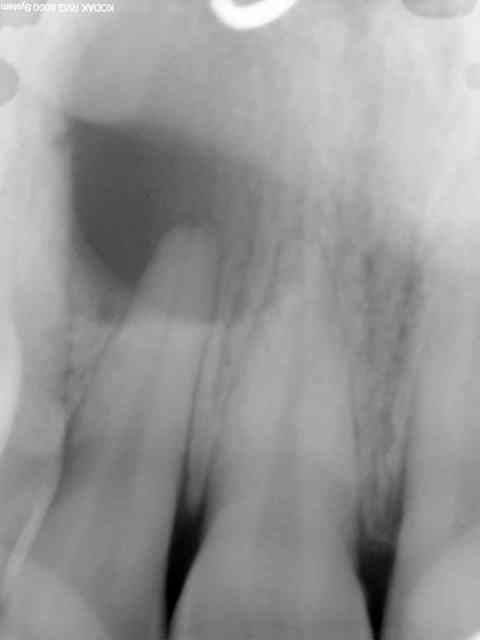

Sinon l'hypothèse diagnostic fut radiologique étant donné la localisation et la confirmation revenant à l'anapath.

Mais attention le radiologue n'avait pas su lire le scanner et avait parlé d'un seul kyste bilobé... je ne lui jette aucunement la pierre, ils n'ont jamais appris la sphère buccale. Je dis juste cela pour rappeler à mon goût l'importance de sa propre analyse des RX en préop

si la dent au milieu est une 12 et que toutes les dents autour sont vivantes, cette localisation ne correspond pas à un kyste dysembryoplasique.

la dent est une 12 le kyste se manifeste en vest haut et en voussure palatine toutes les dents ont un test de vitalite au froid positif de pm a pm poutant l apex de la &é semble bien ouvert pour une patiente de 30 ans ?????

faut voir l'aspect radio à l'OTP

faudra probablement dévitaliser au moins la 12 avant d'énucléer la lésion.

J'ai donc finalement demandé un dentascan en préopératoire...